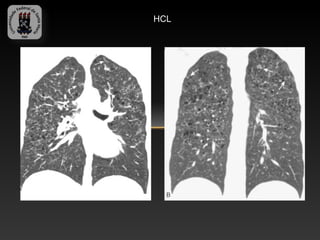

-HISTIOCITOSE DE CELS DE LANGERHANS

-Patologia de adultos jovens fumantes de 30 – 40 anos.

-Caracterizada pelo acúmulo de cels de Langerhans na superfície epitelial

do trato respiratório.

-Achados TC:

-   Micronodulos centrolobulares

-   Cistos lisos que coalescem e formam espaços aéreos bizarros

-   Predominam nas regiões superiores e geralmente os seios

costofrênicos são poupados.

HCL